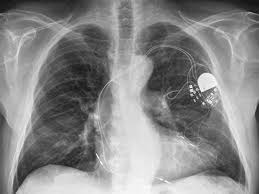

부정맥이 있더라도 증상이 없을 경우 대부분 치료가 필요하지 않지만 심각한 부정맥의 경우 증상이 없거나 매우 경미하더라도 실신이나 돌연사 예방을 위해 치료해야 한다. 증상을 동반하는 병적인 느린 맥의 치료방법은 인공심박동기가 유일하다고 한다.

심장마비의 위험이 큰 환자들의 경우 삽입형 제세동기를 삽입한다. 삽입형 제세동기는 위험한 부정맥을 전기충격으로 소멸시키는 기계적 장치라고 한다.

환자에서 심실빈맥이나 심실세동과 같은 위험한 부정맥이 발생하면, 이를 스스로 감지해 전기충격을 가함으로써 환자의 생명을 구할 수 있다고 한다.